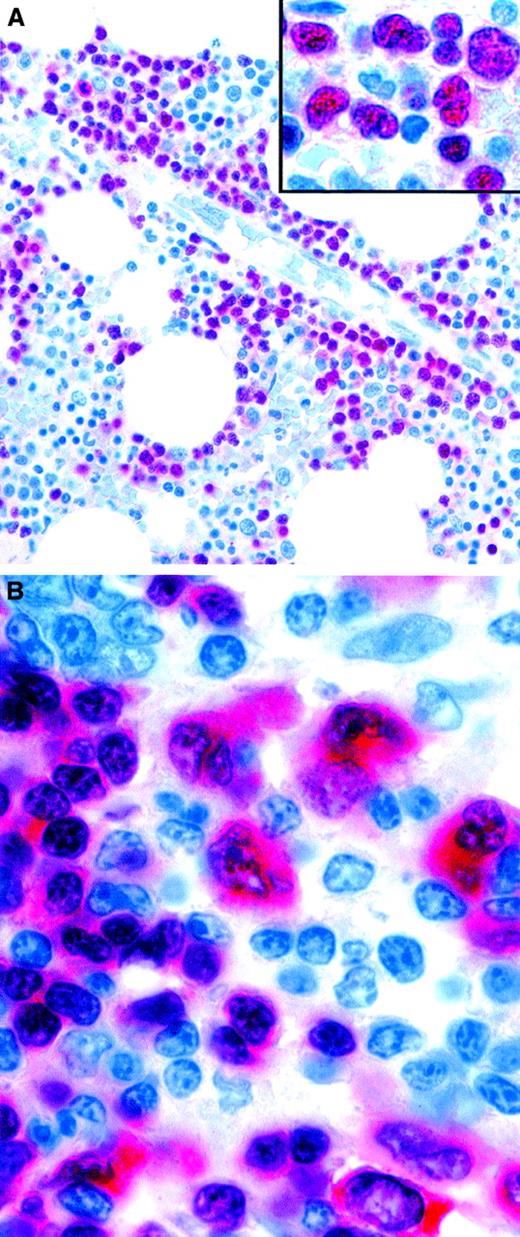

Expression of the plasma cell–associated marker MUM1/IRF4 in neoplastic lymphoid cells.

(A) Bone marrow biopsy specimen showing infiltration by multiple myeloma. Monoclonal MUM1/IRF4 is present in the nuclei and the perinuclear area in neoplastic plasma cells. Residual hemopoietic elements are unlabeled. The inset shows higher magnification-view of the same field. (B) Strong labeling of tumor cells in classic HD (APAAP technique in paraffin sections). Original magnification A, × 600; A inset, × 1000; B, × 1000.

Because of the restriction of MUM1/IRF4 to late-stage B cells, it is potentially valuable (used in combination with other plasma cell markers, such as CD138) for recognizing myelomas (Figure4A). Furthermore, its consistent expression in neoplastic cells in HD (Figure 4B) can be of diagnostic help when the staining highlights Reed-Sternberg and Hodgkin cells in a tissue biopsy specimen (eg, of bone marrow).